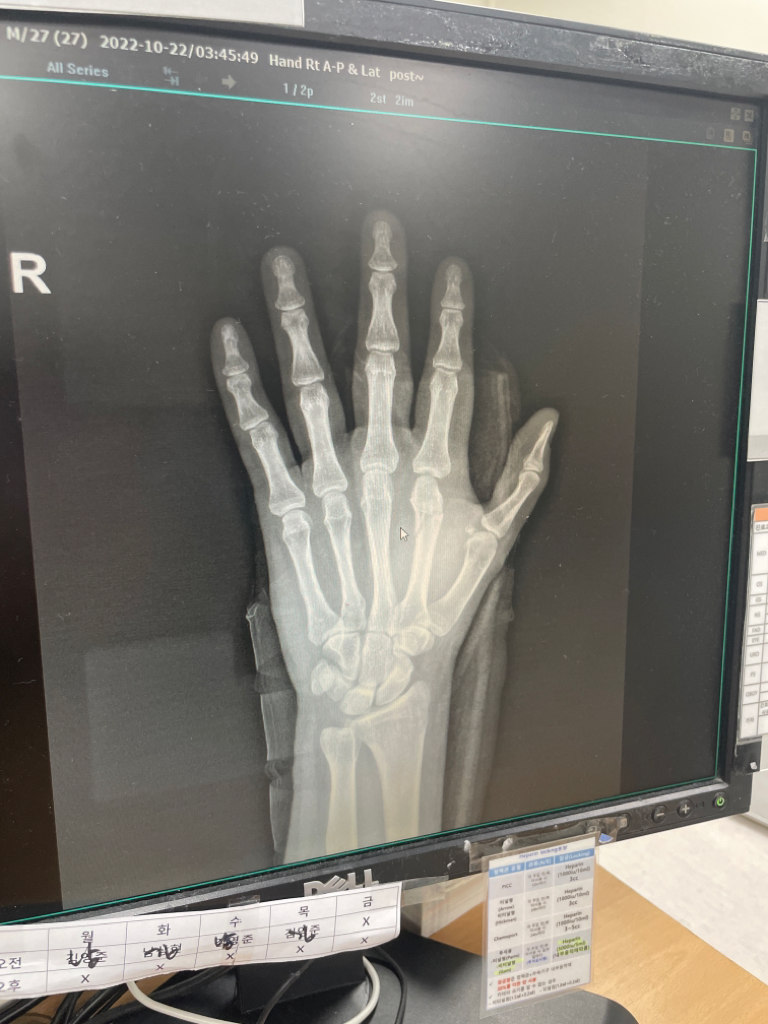

오른쪽 두번째(검지) 중수부 골절입니다ㅜㅜ 질문드립니다

골절이 심한가요ㅜㅠ 수술해야할까요..지금 반깁스상태입니다 월요일에 당장 출근인데 걱정이 이만저만이 아닙니다 지금...

• 1번 째 사진

현재로서는 사진상 명확히 확인이 어렵습니다. 중수골 골절이 보이며 선상 골절은 아닌 상태로 보여 유합에 어려움이 예상된다면 수술이 장기적으로 선호될 수 있겠습니다. 손 부위는 기능을 많이 하는 부위이므로 해당 주치의와 긴밀히 상의 후 결정하시는 것이 좋겠습니다.

뼈가 크게 어긋나지 않을 것으로 보아 심하지는 않습니다.

당장은 수술보다 경과를 지켜볼 수 있으며 두번째 손가락의 움직임이 적은 뼈이기

때문에 깁스 상태로도 회복할 가능성도 높습니다. 깁스는 손가락 골절의 경우 2~4주,

인대 손상은 3~6주 정도를 하게 되는데 대부분 깁스만으로도 회복하는 모습을

보이게 됩니다.

수술을 하지 않으시면 한동안 고정을 해놓으셔야하고 굳어버린 관절로 인해 재활치료를 한동안 하셔야할겁니다.

움직임이 많은 손뼈이기에 수술을 하고 조기에 손을 움직이고 재활치료를 하시는게 적절할것으로 판단되지만 정확한건 정형외과 선생님의 소견을 들어보시는게 맞겠습니다.